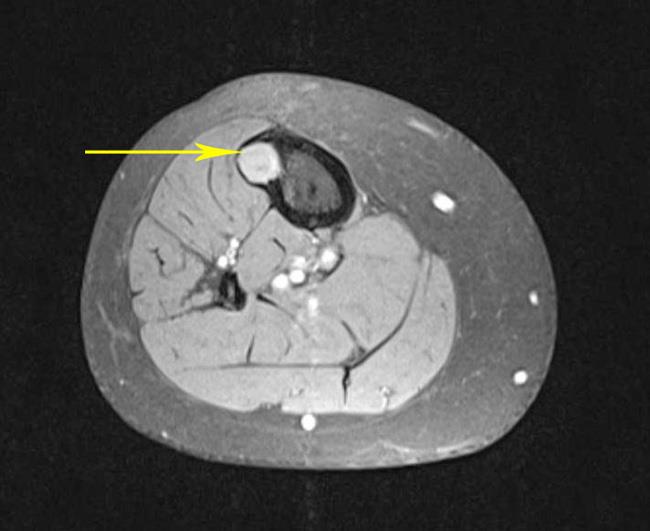

Η μαγνητική τομογραφία (MRI) είναι μια άλλη διαγνωστική τεχνική απεικόνισης που παράγει εικόνες εγκάρσιας τομής του σώματός σας. Σε αντίθεση με τις ακτίνες Χ και τις αξονικές τομογραφίες, οι μαγνητικές τομογραφίες λειτουργούν χωρίς ακτινοβολία. Το εργαλείο μαγνητικής τομογραφίας χρησιμοποιεί μαγνητικά πεδία και έναν εξελιγμένο υπολογιστή για να λαμβάνει εικόνες υψηλής ανάλυσης των οστών και των μαλακών ιστών σας.

Μια άλλη κάπως πρόσφατη εξέλιξη είναι η βελτιωμένη δυνατότητα σάρωσης μιας άρθρωσης που έχει αντικατασταθεί. Οι τεχνητές αρθρώσεις περιέχουν πολύ μέταλλο, το οποίο μπορεί να προκαλέσει θολές εικόνες στις μαγνητικές τομογραφίες, καθιστώντας πιο δύσκολο να εντοπιστεί η ζημιά στην περιοχή γύρω από το εμφύτευμα. Ορισμένες νεότερες μηχανές μαγνητικής τομογραφίας διαθέτουν λογισμικό, που ονομάζεται ακολουθίες μείωσης μεταλλικών τεχνουργημάτων ή MARS, το οποίο μειώνει το θάμπωμα των εικόνων. Το MARS μπορεί να χρησιμοποιηθεί σε ορισμένους ασθενείς για να βοηθήσει στη διάγνωση ορισμένων παθήσεων. Η εκτέλεση αυτής της σάρωσης δεν χρειάζεται περισσότερο χρόνο και δεν υπάρχει πρόσθετος κίνδυνος για τον ασθενή.